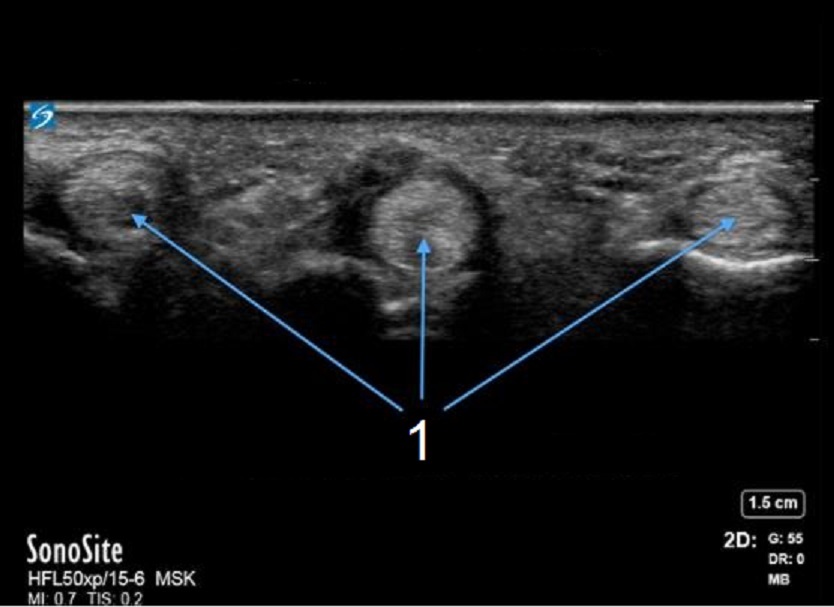

手部 A1 滑车屈肌腱横切面图像

增厚的 A1 滑车

屈肌腱横断面